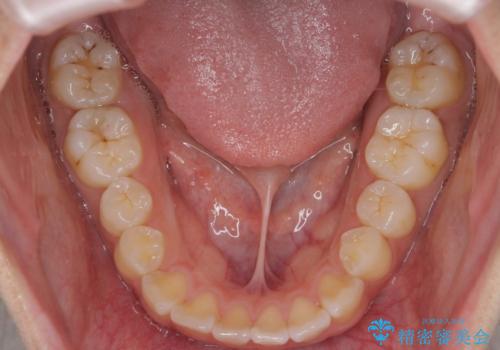

- 前歯の目立つねじれを矯正治療で治したい、と来院されました。

マウスピース矯正を始める前に、ねじれを取るのが短期間で済む部分ワイヤー小矯正を行うことで、全体的な治療期間を短くする治療計画を実行していきます。

前歯のねじれはマウスピース矯正の苦手な動きになり、治療期間が長くなる原因になりやすいです。